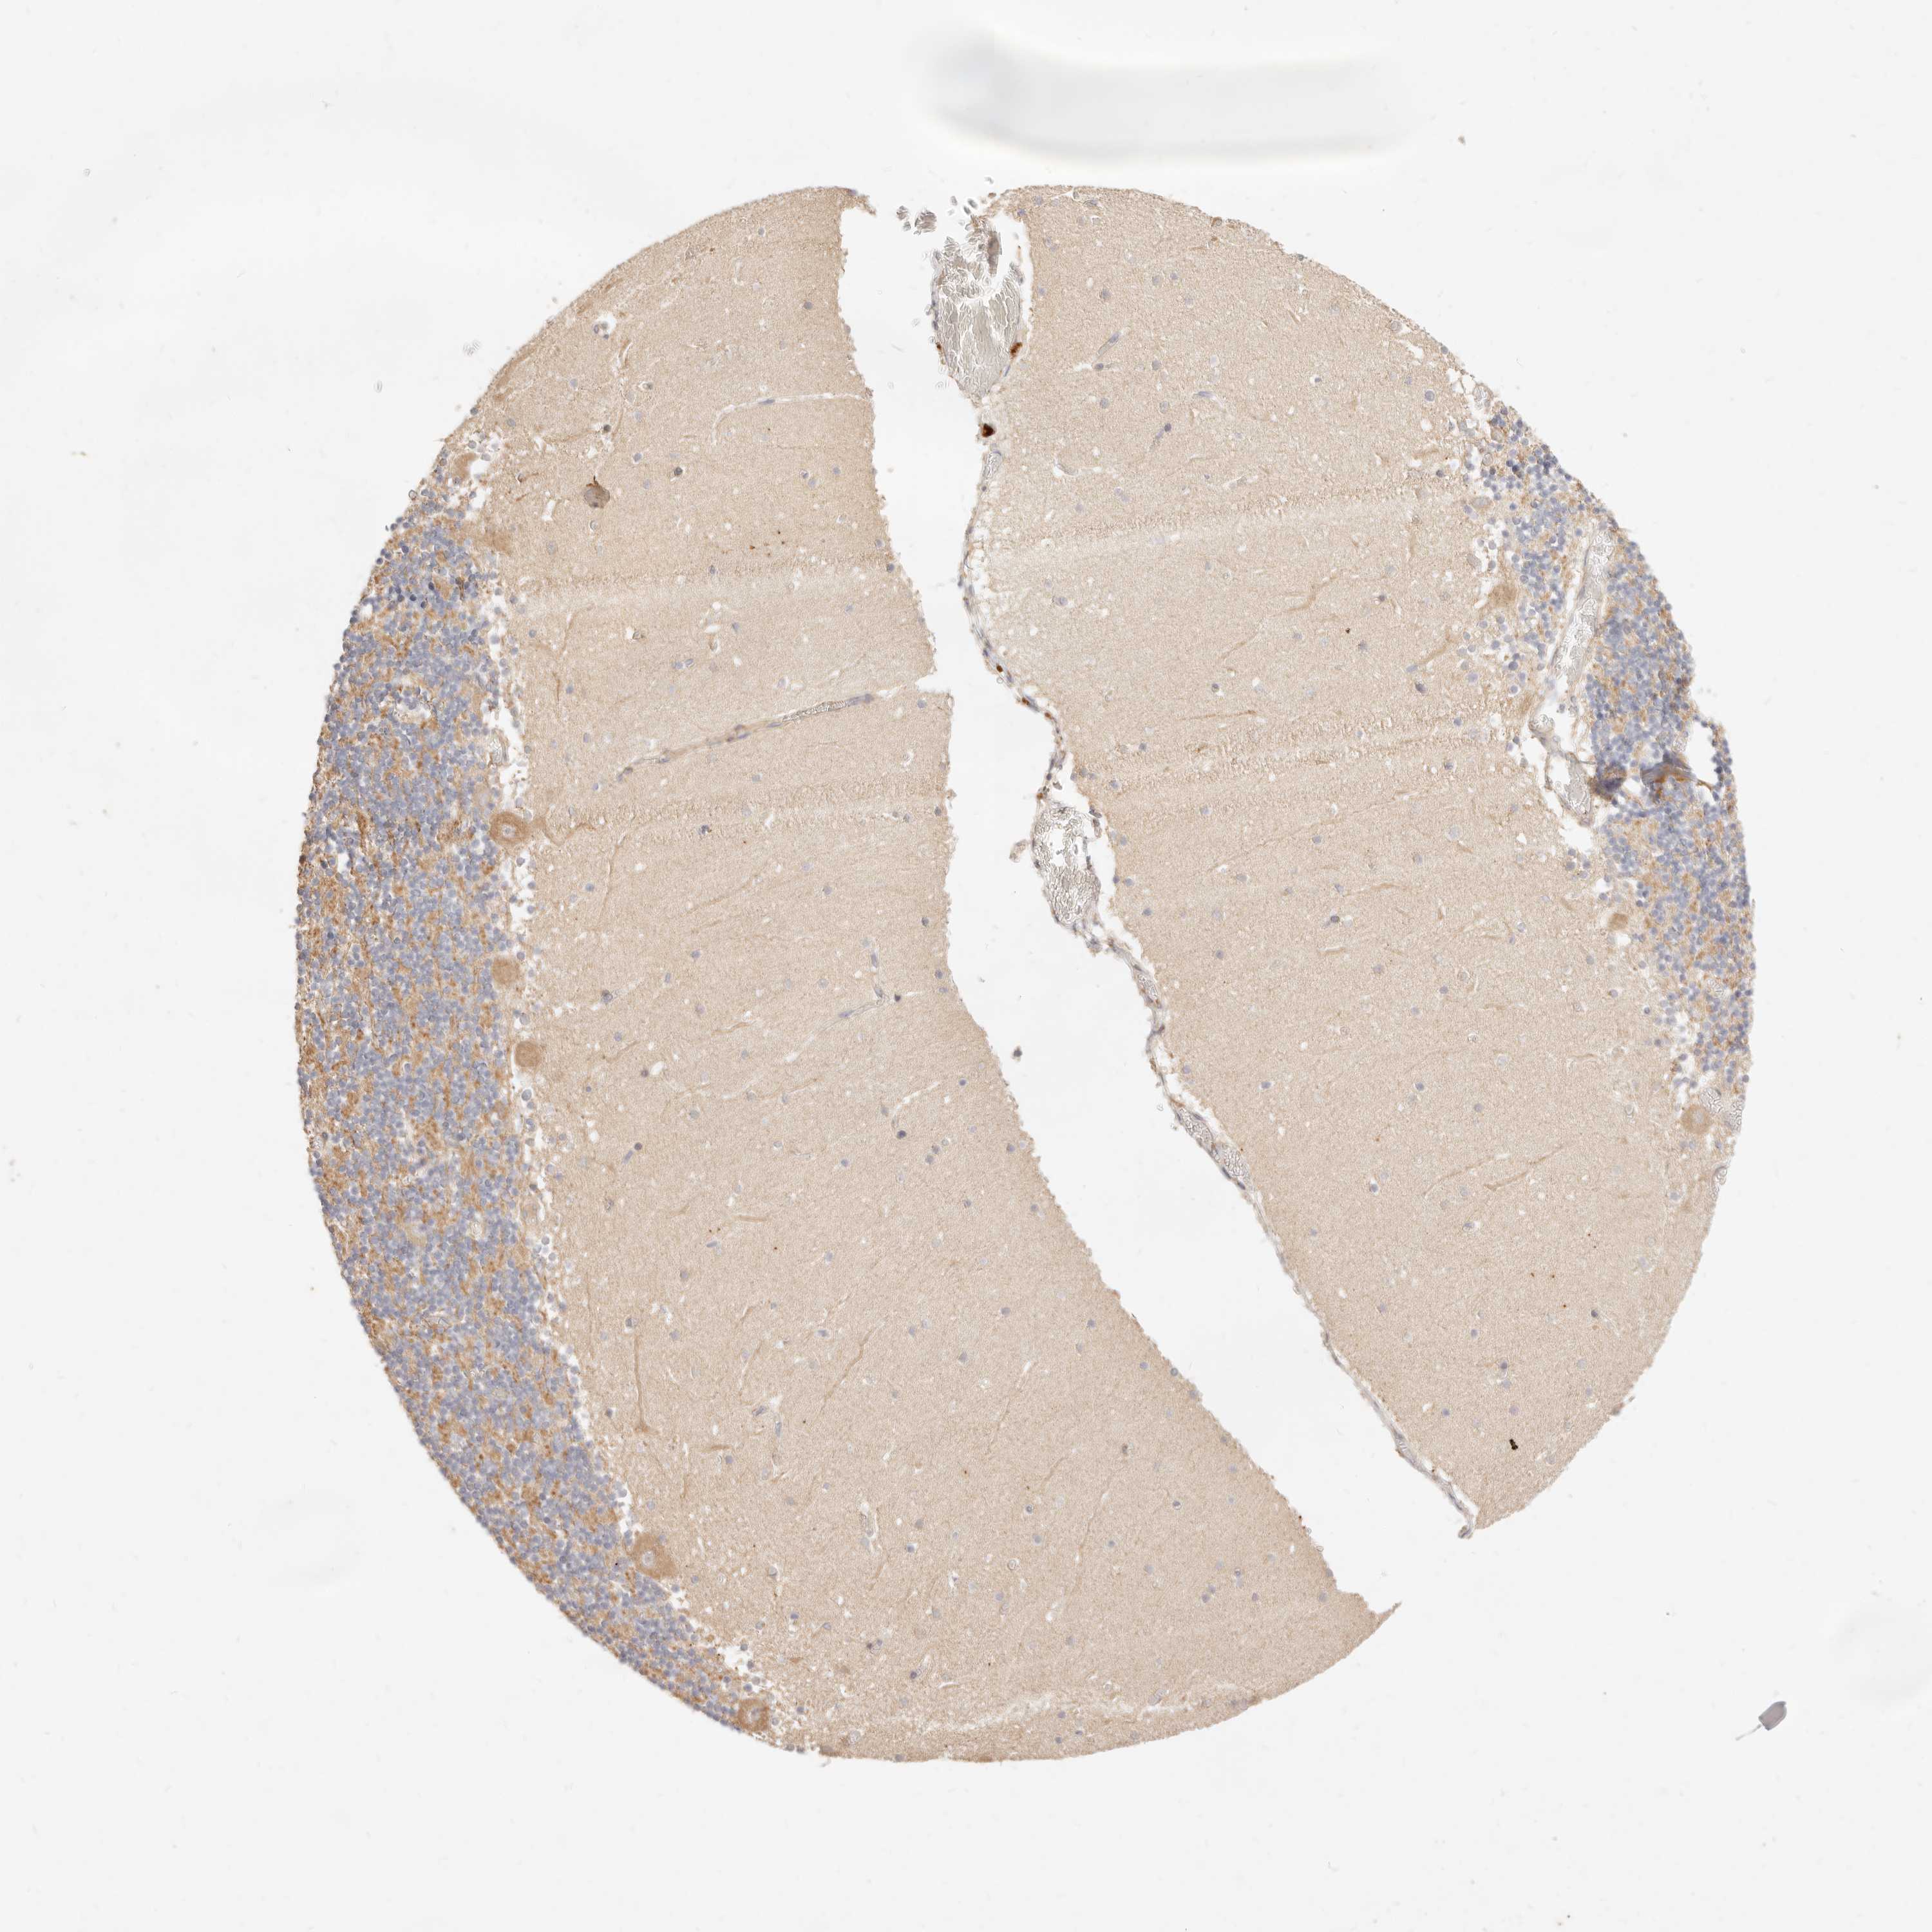

CEREBELLUM - Antibody stainingi

Antibody staining in the annotated cell types in the current human tissue is reported as not detected, low, medium, or high, based on conventional immunohistochemistry profiling in selected tissues. This score is based on the combination of the staining intensity and fraction of stained cells.

Each image is clickable and will lead to virtual microscopy that enables deeper exploration of all samples and also displays staining intensity scores, fraction scores and subcellular localization as well as patient and tissue information for each sample.

Antibody HPA026614

Purkinje cells Medium

Cells in granular layer Medium

Cells in molecular layer Low